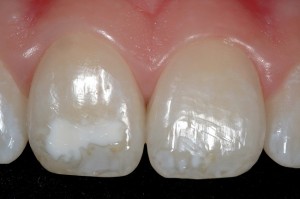

Очаговая гипоплазия

Очаговая гипоплазия. Проявляется нарушением развития тканей зуба преимущественно в одном или нескольких зубах одновременно. Возникает в результате травмы фолликула, под влиянием хронического воспаления в периодонте молочного зуба или опухоли челюсти.

Клиническая картина. В молочных зубах встречается в результате травмы зачатка при переломе челюсти, когда линия перелома проходит через фолликул зуба. Фолликул постоянного зуба может повреждаться при вколоченном вывихе молочного зуба. В зависимости от стадии развития зачатка, силы удара и места приложения силы возникают изменения тканей зуба различной интенсивности. Местная гипоплазия тканей зуба в результате влияния очага хронического воспаления при хроническом периодонтите, остите или остеомиелите челюсти чаще наблюдается на премолярах, так как соответствующие им молочные моляры чаще поражаются кариесом, следовательно, и периодонтитом.

Имеет значение и топографическое соотношение корней молочных зубов и зачатков постоянных. Травма и инфекция нарушают функцию амелобластов, в тяжелых случаях и одонтобластов, в результате чего эмаль и дентин формируются необычно и зуб приобретает неправильные форму, вид. Такие зубы получили название зубов Турнера, по имени автора, описавшего впервые эту разновидность патологии.